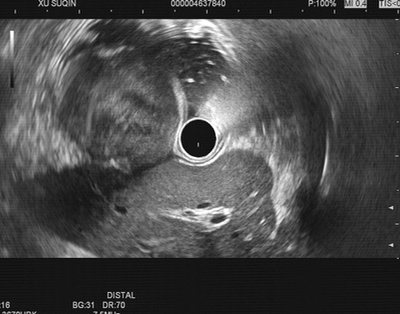

超声胃镜下的瘤体

患者徐××,女,62岁。以上腹不适10余天之主诉入院。10余天前因食枣后出现上腹不适,就诊于当地医院。行胃镜检查示胃内异物、慢性浅表性胃炎、胃体粘膜下肌瘤?并将枣核取出,症状好转。现为明确胃体肿物性质就诊于我院。消化科超声胃镜检查见:胃体底交界前壁小弯侧光滑粘膜隆起性病变,超声扫描见局部胃壁层次清晰,固有肌层可见低回声占位,最大截面约35×25mm,内部回声不均匀,可见不规则无回声区及高回声斑,其余各层未见异常回声。诊断为胃底体交界粘膜下隆起性病变考虑间质瘤。遂门诊以“胃间质细胞瘤”收住入院。入院查体无阳性体征。血、尿、粪常规、凝血功能、肝炎系列+HIV+TP及肿瘤系列未见明显异常,胸片、腹部彩超未见明显异常。经与主管医师组讨论,可行内镜下切除术。但瘤体巨大,且侵及胃壁肌层,完整切除需行经胃镜下全层切开(EFTR)术,可能胃壁切口较大,必要时需请外科腹腔镜联合手术,缝合胃壁切口。经与患者及家属充分告知谈话后,患者及家属同意胃镜下手术。